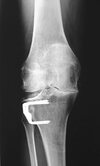

what is this finding called? association?

A

Segund fx

bony aculsion of anterolateral ligament

pathognominic for acl tear

associated with acl tear 75-100 percent of the time.